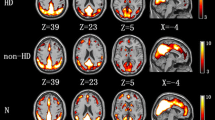

Common brain activity patterns of SWM

Correlation analysis was performed to generate brain activation maps for each group, and further address the brain regions of interest (ROIs). The average BOLD response amplitude of each subject’s ROIs in the three n-back conditions was calculated, and showed common brain activity patterns during the n-back task in both the HD-ESRD patients and control group, including the superior/middle/ inferior frontal gyrus (SFG/MFG/IFG), superior/inferior parietal lobule (SPL/IPL), anterior/posterior cingulate cortex (ACC/PCC) and insula cortex, with right hemispheric dominance. We defined these common brain activity regions as regions of interest (ROIs) of SWM (Fig. 2), which are also reported in previous studies on working memory using n-back tasks (Huang et al. 2016; Liao et al. 2012; Yin et al. 2012).

Regions of interest (ROIs) of spatial working memory. fMRI examination revealed common brain activity patterns during the n-back task in both the HD-ESRD patients and control group, including the SFG/MFG/IFG, SPL/IPL, ACC/PCC and insula cortex, with right hemispheric dominance. These brain regions were consistent with those previously reported in studies of working memory so we defined these common brain activity regions as regions of interest (ROIs) of spatial working memory (SWM). L, left hemisphere; R, right hemisphere; SFG, superior frontal gyrus; MFG, middle frontal gyrus; IFG; inferior frontal gyrus; SPL/IPL, superior/inferior parietal lobule; ACC, anterior cingulate cortex; PCC, posterior cingulate cortex

In this study, fMRI examination revealed similar brain activity patterns during the n-back task in both HD-ESRD patients and controls, including the SFG/MFG/IFG, SPL/IPL, ACC/PCC and insula cortex, with right hemispheric dominance, consistent with brain regions previously reported in studies of working memory (Nystrom et al. 2000; Ray et al. 2008). Therefore, we defined these brain regions as regions of interest (ROIs) of SWM .